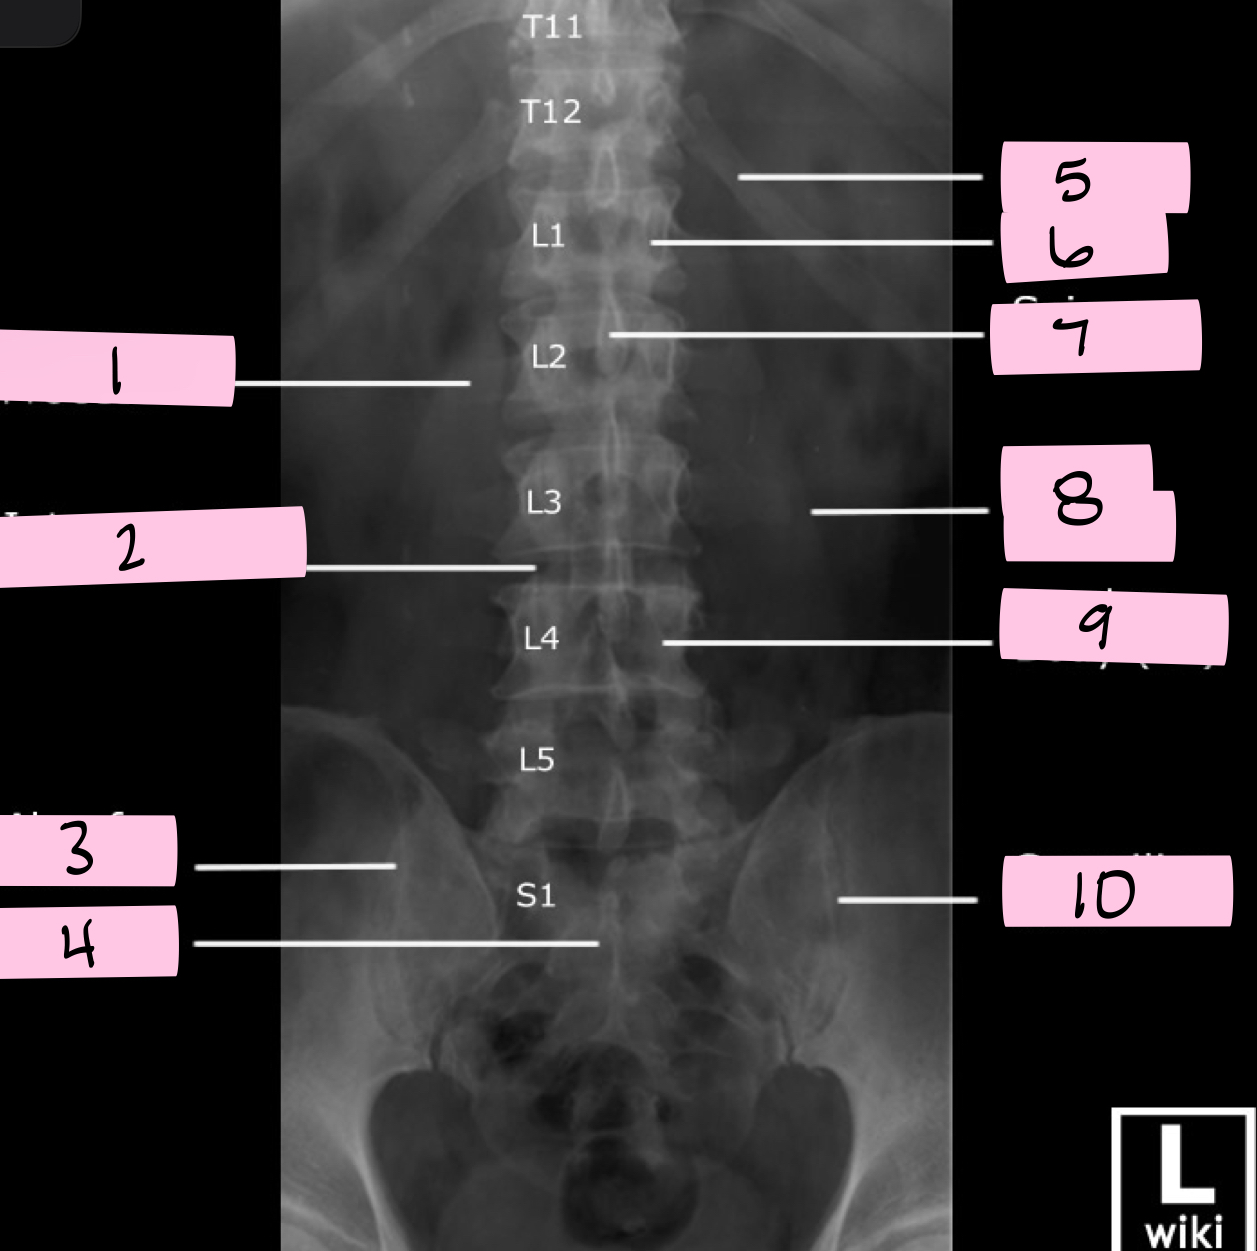

What is 1 pointing to?

Transverse process

What is 2 pointing to?

Intervertebral disk

What is 3 pointing to?

Ala of sacrum

What is 4 pointing to?

Sacrum

What is 5 pointing to?

12th Rib

What is 6 pointing to?

Pedicle

What is 7 pointing to?

Spinous process

What is 8 pointing to?

Psoas muscle

What is 9 pointing to?

Lumbar body (L4)

What is 10 pointing to?

Sacroiliac joint